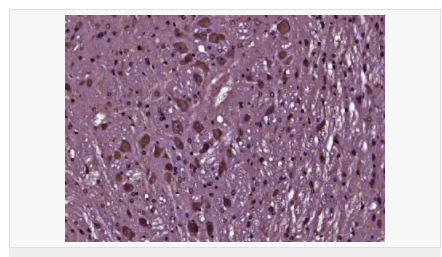

image.png